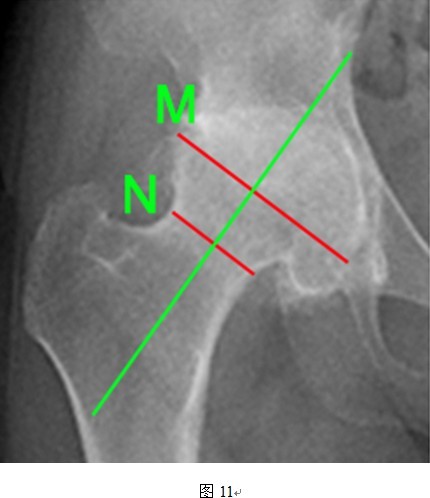

(2)异常头颈比常导致术后人为股骨颈缩窄

THRA的假体设计要求,头颈比为1.2:1的髋关节对于THRA手术最为适合,但是本组数据达到平均1.47(图11所示病例为典型头颈比增大),可能与DDH的病理特点有关。大头颈比情况下,股骨颈相比之下则显得纤细,造成术后股骨颈人为缩窄现象。目前认为股骨颈骨折主要与股骨颈上部切迹和股骨假体内翻放置有关,尚未有文献提及宿主头颈比、人为股骨颈缩窄对术后假体存活、股骨颈骨折的影响,二者间的联系尚待进一步证实。

④头颈比:M/N的数值(M线为股骨头直径,N线为股骨颈直径);

DDH患者股骨头往往变扁增宽,图中股骨头直径与股骨颈直径的比例(M/N)远远超过1.2:1。